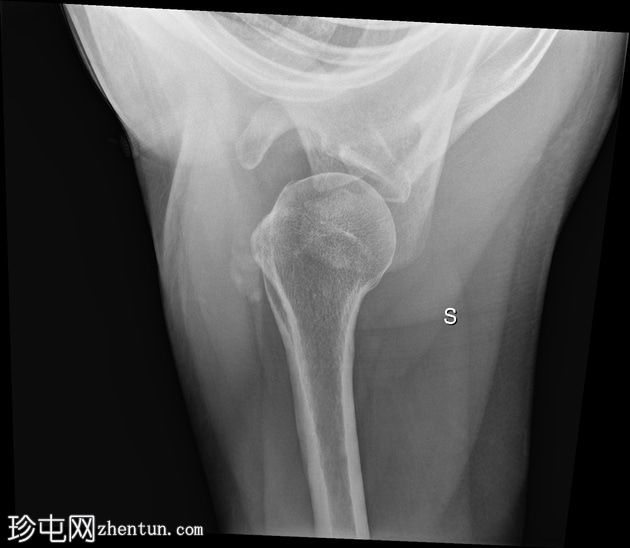

X线片

正位 -

内旋位

可见肱骨头周围、三角肌腱和冈上肌腱之间有钙化沉积物,呈致密均匀的阴影。